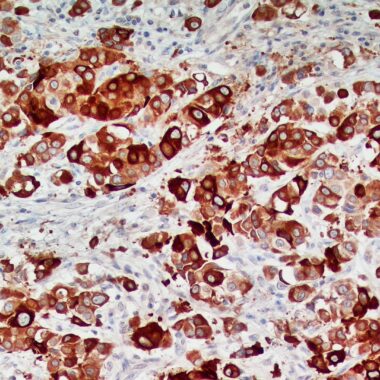

Zeta Uroplakin II Antibody. Zeta’s rabbit recombinant antibody recognizes Uroplakin II (UPKII), a 15-kDa transmembrane protein and member of the uroplakin family (other two components are uroplakin I and uroplakin III), primarily expressed in urothelial (transitional) epithelium. Uroplakin II is a highly specific marker for tumors of urothelial origin, particularly urothelial carcinoma (UC). Immunohistochemistry utilizing UPII antibodies exhibits high specificity for urothelial carcinoma compared to UPK I, UPK III, and GATA3. UPII immunohistochemistry is valuable for differentiating urothelial carcinoma from other malignancies, including prostate adenocarcinoma or metastatic breast carcinoma. It has also shown promise for detecting micrometastases of bladder cancer. UPII expression is found in various UC subtypes like micro-papillary, plasmacytoid, and sarcomatoid variants.

Uroplakin II is a highly specific marker for urothelial differentiation is and is positive in most primary urothelial carcinomas (including high-grade and invasive types) and retains expression even in poorly differentiated urothelial tumors.  Additionally, Uroplakin II can help distinguish metastatic urothelial carcinoma from morphologically similar carcinomas (e.g., ovarian serous carcinoma, prostatic adenocarcinoma, colorectal adenocarcinoma) as it is more specific than GATA3 in certain settings, though less sensitive.

Control:Urothelial carcinoma

Visualization:Cell membranous